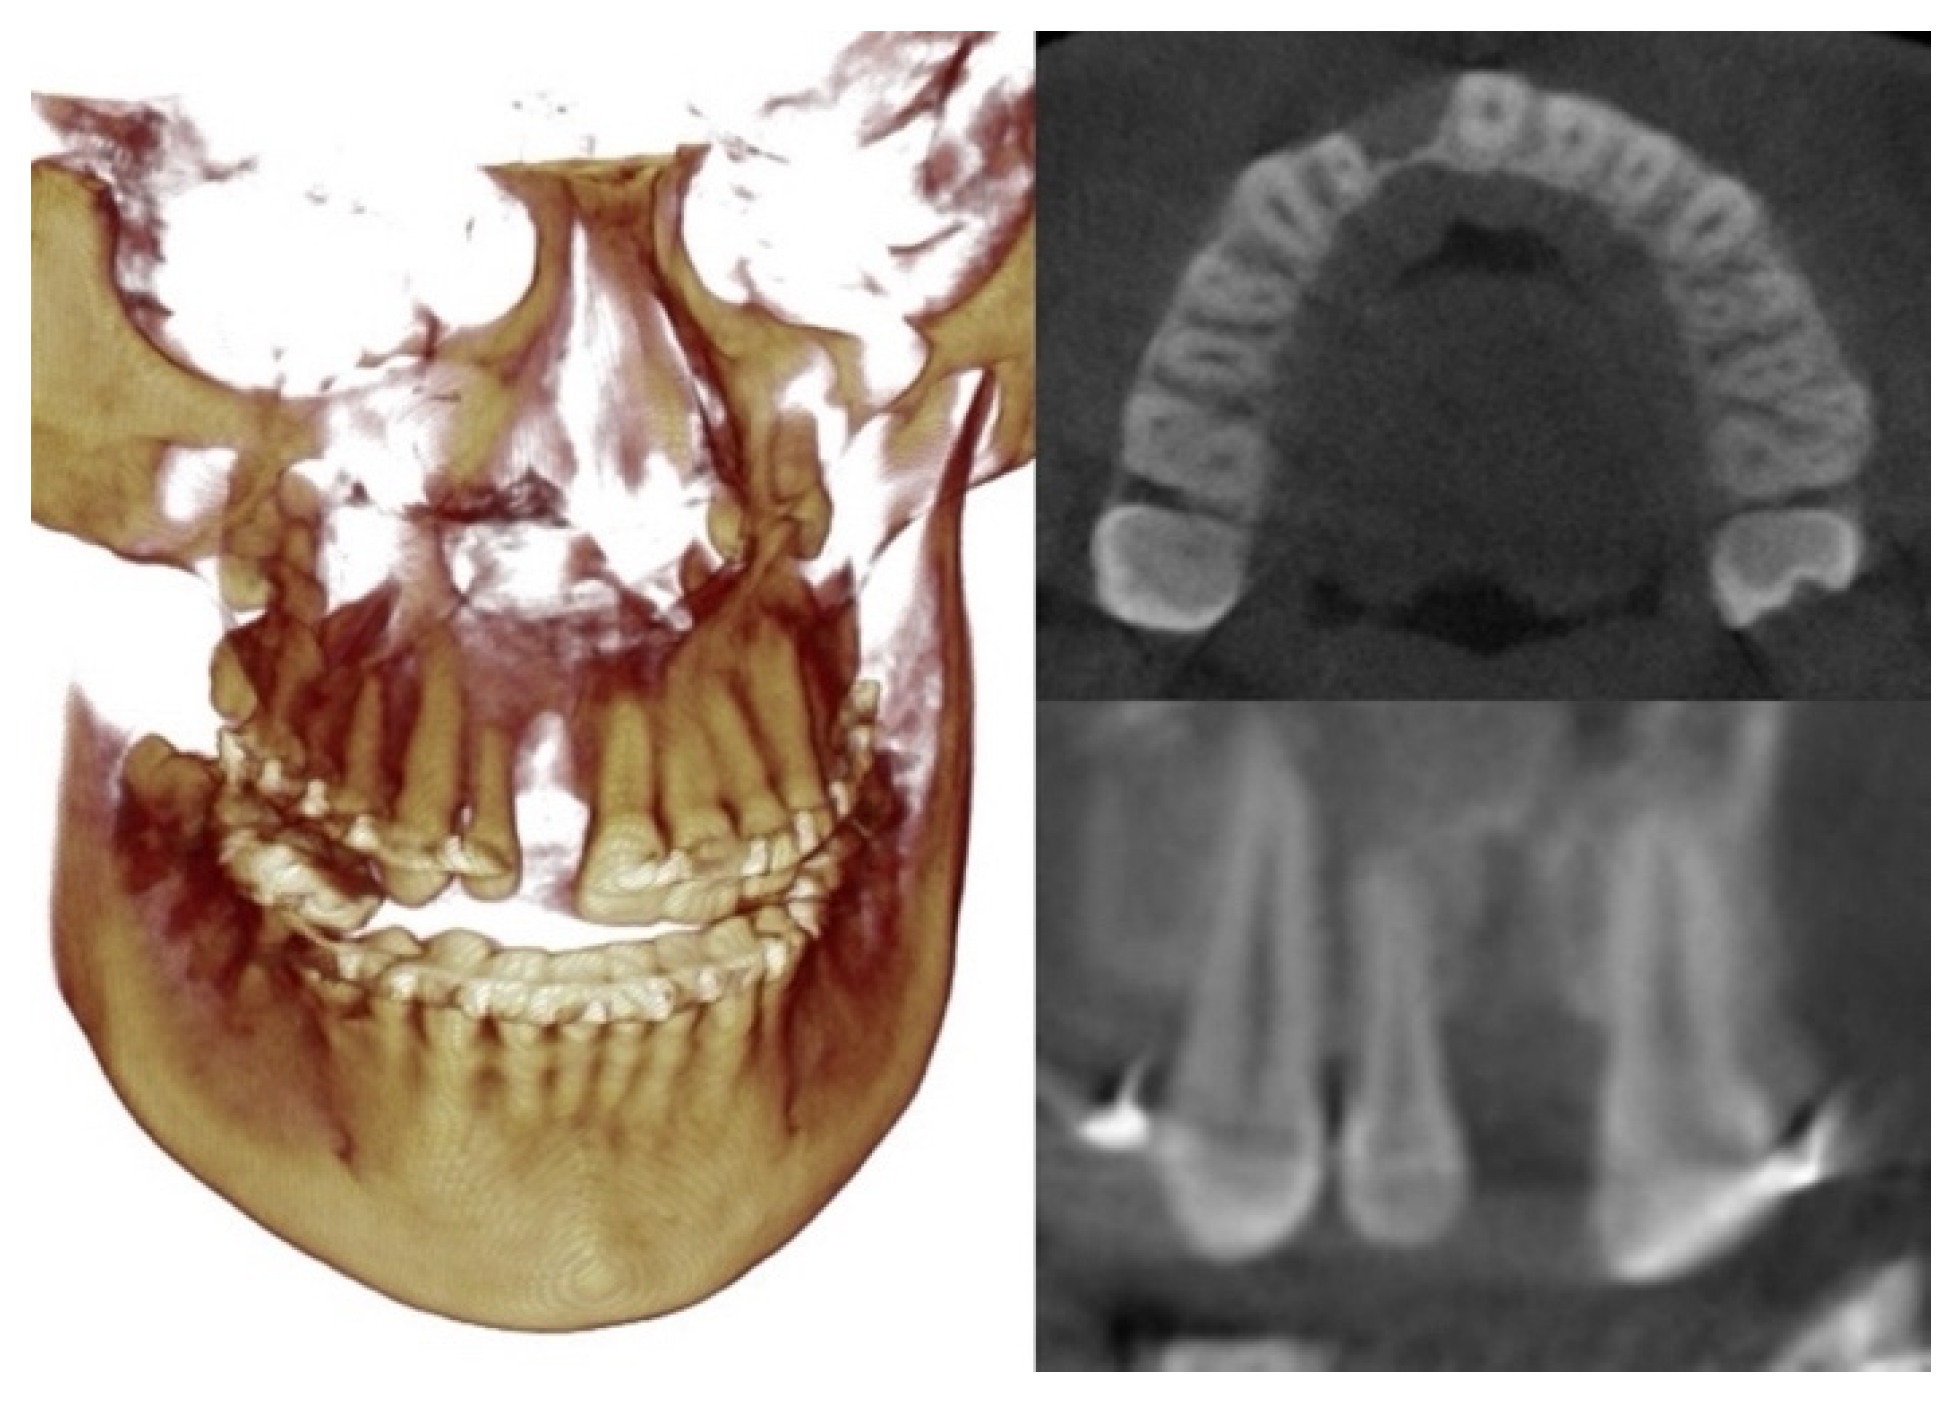

2. Case Description

| SNA (°) | 82.0 ± 3.5 | 78 |

| SNB (°) | 80.9 ±3.4 | 87.7 |

| ANB (°) | 1.6 ± 1.5 | −9.7 |

| A-Na Perpendicular (mm) | 1.1 ± 2.7 | 2.4 |

| Pog-Na Perpendicular (mm) | −0.3 ± 3.8 | 30.5 |

| Co-A (mm) | 99.8 ± 6.0 | 79.8 |

| Co-Gn (mm) | 134.3 ± 6.8 | 132.6 |

| Co-Gn—Co-A (mm) | 34.5 ± 4.0 | 52.8 |

| Wits (mm) | −1 ± 1.0 | −17.4 |

| SN-MP (°) | 33.0 ± 6.0 | 27.1 |

| Dental | ||

| U1-SN (°) | 103.1 ± 5.5 | 108.3 |

| L1-MP (°) | 95.0 ± 7.0 | 83.2 |

| Soft tissue | ||

| Upper lip to E-line (mm) | −4.0 ± 2.0 | −14.7 |

| Lower lip to E-line (mm) | −2.0 ± 2.0 | −5.3 |